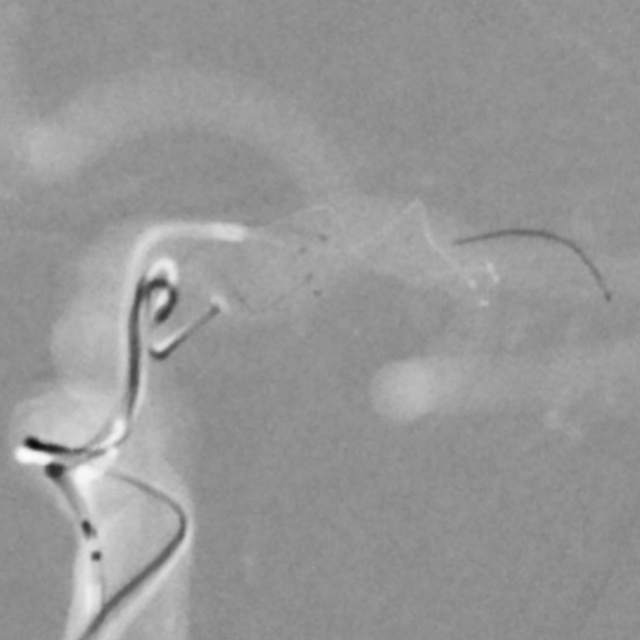

手术过程:术中采用“一个支架+一个弹簧圈”的简约模式顺利结束手术,消除了动脉瘤破裂出血的风险。

手术结果:本次手术具有“创伤小、花费少、时间短、出院快”的特点,而且支架紧邻分叉部近段,没有覆盖大脑前动脉、支架打开贴壁良好、所有分支保持通畅~~~

手术难点:支架远端超过分叉部,操作简单;支架远端若紧邻分叉部近段,操做要求高。